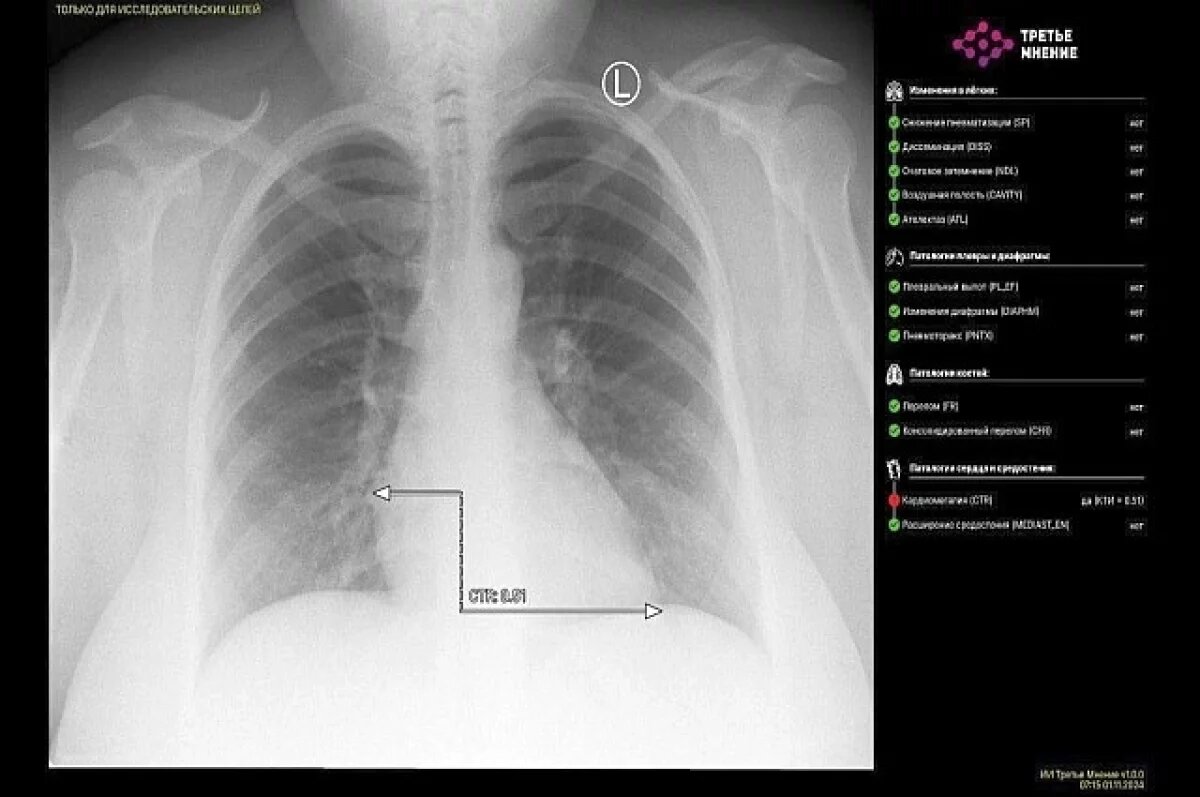

В уфимской больнице №21 искусственный интеллект за минуту расшифровал снимок рентгена пациента. В Башкирии подобное произошло впервые, сообщил министр здравоохранения Айрат Рахматуллин.

По его словам, ИИ интерпретировал полученное медицинское изображение, разметил зоны патологических очагов и выдал протокол исследования.